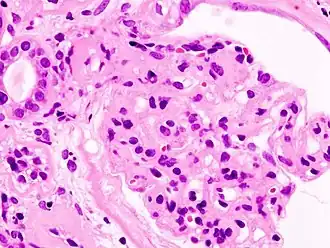

L'ultrafiltration du sang qui va donner l'urine primitive se fait dans le glomérule. Par un mécanisme physique (pression hydrostatique, pression oncotique) et biologique (sélectivité de la membrane glomérulaire aux composants sanguins), le plasma est filtré à travers la membrane basale glomérulaire (MBG) et les prolongements podocytaires qui la tapissent pour former l'urine primitive, laquelle sera ensuite successivement modifiée par les différentes structures rénales pour donner l'urine définitive. Le syndrome néphrotique est dû à une anomalie anatomique ou fonctionnelle de la membrane basale glomérulaire, qui est normalement imperméable aux protéines au-dessus d'un poids moléculaire de 60 kDa (60 000 daltons). La perte de cette sélectivité entraîne le passage de protéines dans les urines (qui apparaît lorsque les capacités physiologiques de réabsorption tubulaire des protéines sont dépassées), et donc la protéinurie et l'hypoprotidémie (malgré une synthèse accrue de protéines par le foie).

Un examen simple permet de différencier ces deux tableaux : l'évaluation de la sélectivité de la protéinurie. Une protéinurie composée à plus de 85 % d'albumine (principale protéine plasmatique) est dite sélective, et relève des anomalies fonctionnelles le plus souvent. Au contraire, une protéinurie non sélective témoigne le plus souvent d'anomalies anatomiques sévères ne touchant pas que la membrane basale glomérulaire.

- Glomérulonéphrite extramembraneuse : par dépôt d'immunoglobulines G et de fractions du complément sérique à la face externe de la membrane basale glomérulaire.